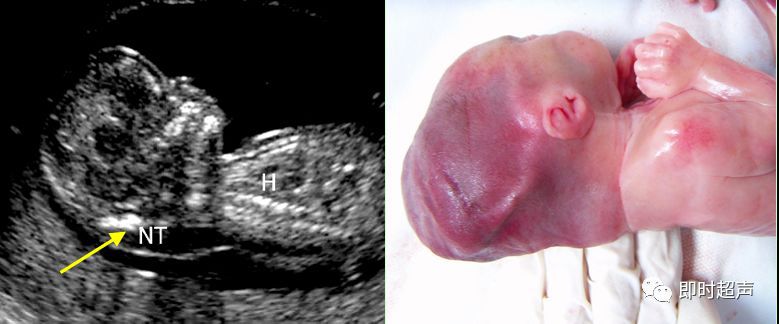

一、颈项透明层

NT定义:颈项透明层指胎儿颈椎水平矢状切面皮肤至皮下软组织之间的最大厚度NT反映皮下组织内淋巴液体的积聚。

测量时间: 在孕 11 – 14周。胎儿头臀长 45 ~84mm时进行。

超声测量NT:多数专家认为NT 增厚定义为厚度超过第 95 百分位数,不论NT 是否有分隔,也不论是局限性或全身性,即 NT≥3.0mm作为异常增厚的标准。

国外的文献报道:>3mm,10%的胎儿有畸形 >6mm,90%的胎儿有畸形。

NT增厚的临床意义:NT增厚与染色体异在孕早期所有的染色体异常都与NT增厚有关,颈项透明层增厚越明显,发生胎儿结构异常与染色体异常的概率越大。NT增厚与胎儿先天性心脏病有关。研究发现颈项透明层增厚胎儿心脏及大血管结构异常的发生率明显增高。